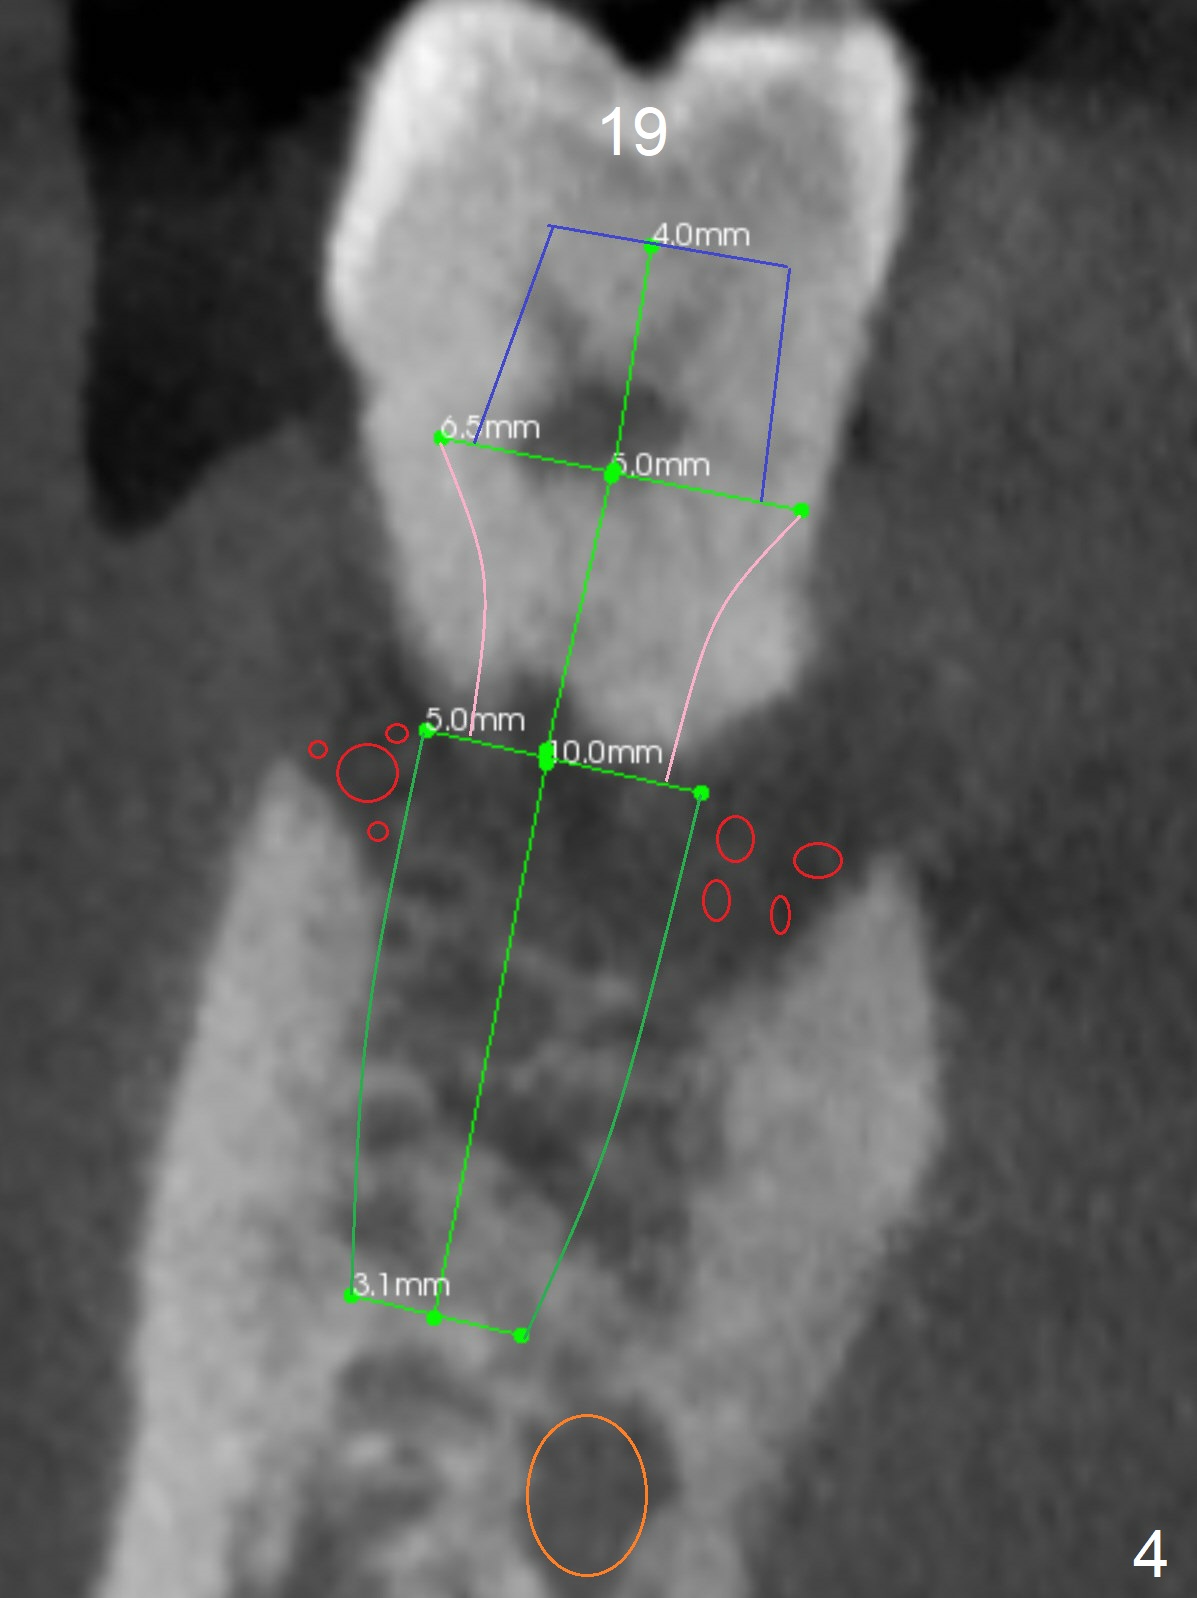

A 36-year-old man develops periodontal abscess at #19 and 20 after scaling & root planing. Since the site of #20 is close to the Mental Nerve, 3.8 mm tap or dummy implant will be used to form osteotomy instead of drills (Fig.1,3). While an implant will be placed in the middle of the socket #20, an implant will be placed as buccal as possible at #19 (Fig.4). If primary stability at #20 is poor, extract the tooth #21 and place a 3.8x10 mm lingually (Fig.2). PRF membrane will be placed prior to bone graft after implant placement (Fig.3 yellow).